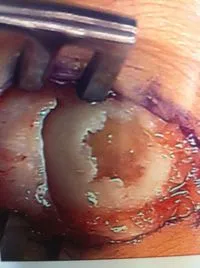

Osteochondral Autograft Transfer System (O.A.T.S.)

There is damage to the articular surface cartilage which can occur either from an acute injury or more commonly after repetitive injury and/or wear and tear. If the bones at the joint in question are not aligned properly, then this mechanically adds to the wear that the joint receives with activity and increases the propensity of this occurring.  Pictured below is linear damage to the articular surface of the second metatarsal head.

The following pictures are debridement of damaged cartilage that is abnormal in appearance and/or loose. This is removed completely to expose the subchondral (underneath cartilage) bone plate.

Drill holes are then placed through the bone plate to allow bleeding in the area, which will aide in healing of the cartilage surface with fibrocartilage, which is a kind of scarring of cartilage.